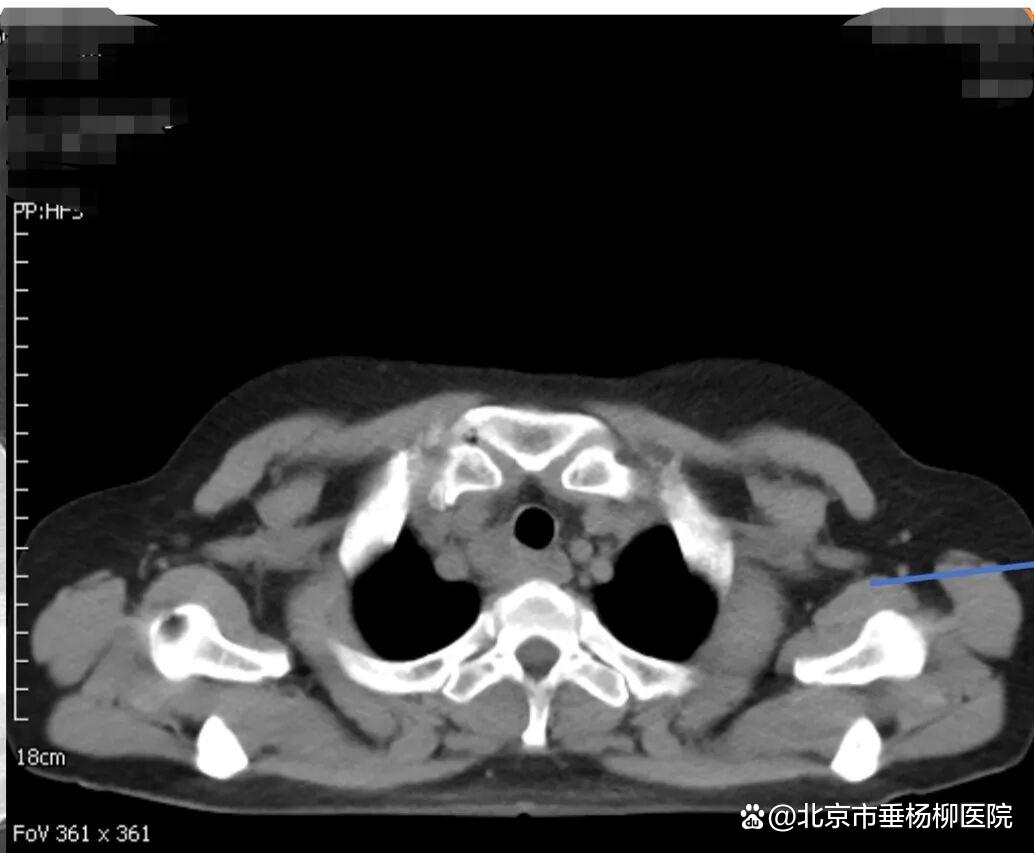

62岁的郑女士近一月来进食时总有食物下咽不畅感,伴有明显哽咽。当地医院胸部增强CT提示食管上段有一约3.7×2.6CM占位性病变,影像报告“不除外食管癌,且可能累及气管后壁”。随后的PET-CT更显示该病灶糖代谢异常增高,代谢活性值高达14.4,强烈指向恶性肿瘤可能。这一系列检查结果让患者及家人陷入焦虑与恐惧。

▲治疗前胸部CT